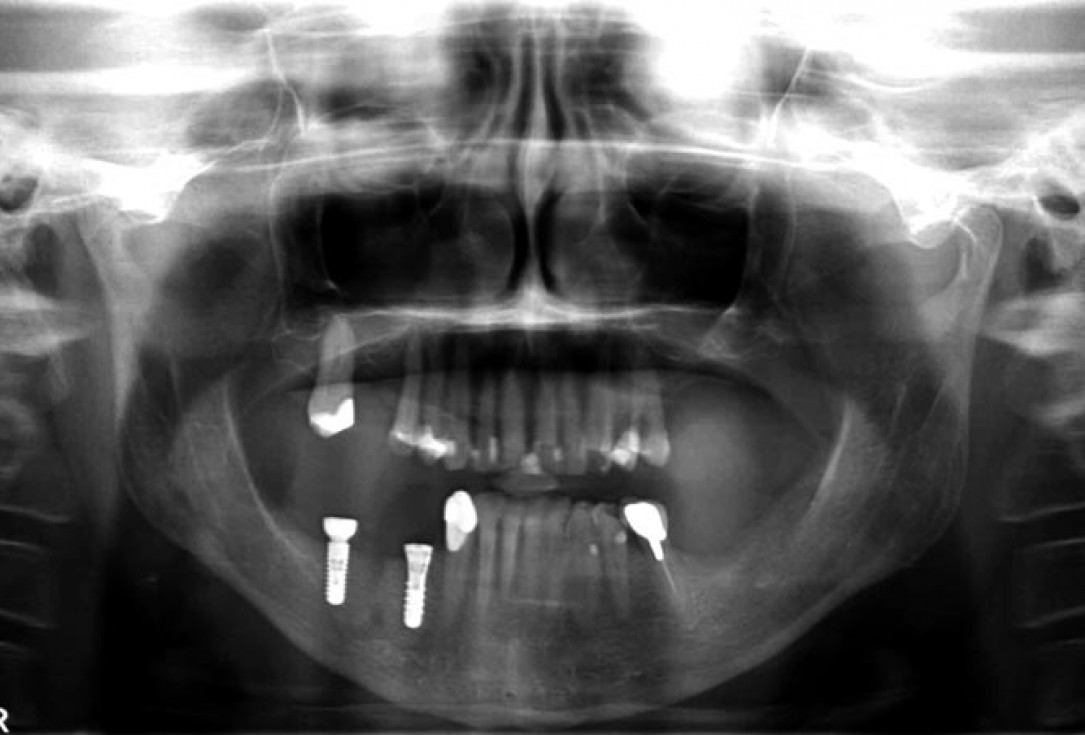

01/14 - Free-end situation in right mandible

Block augmentation with maxgraft® in the mandible - PD Dr. Dr. F. Kloss